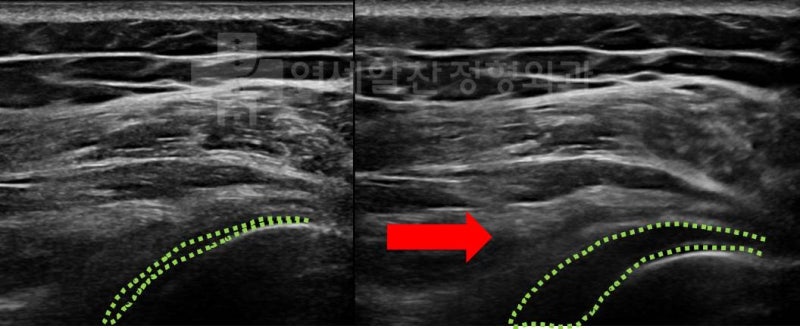

골절이 유합된 상태로 외상(골절)후 장기간 고정에 의한 유착성 관절낭염 진단하에 관절수액팽창술(hydro-dilatation) 및 재활치료를 권고하였다.